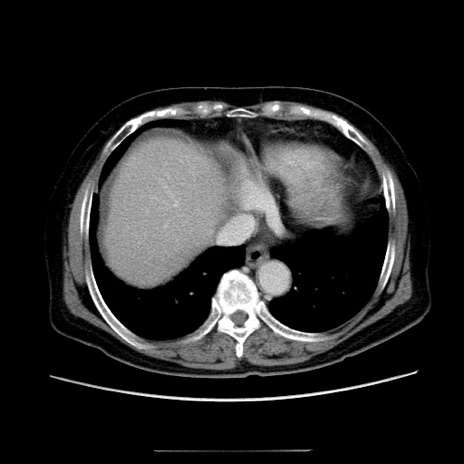

症例5(横断像)

【症例】70歳代女性

【主訴】お腹が張る

【現病歴】1週間くらい前から腹部膨満の自覚あり。昨日夜から増悪したため、本日救急外来受診。

【身体所見】意識清明、BT 36.5℃、BP 165/106mmHg、HR 80bpm、SpO2 98%、腹部:膨満、軟、自発痛・圧痛なし、触診にて不快感あり、腸蠕動音:減弱

【データ】WBC 12600、CRP 1.04